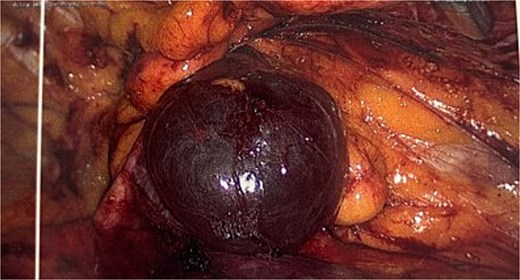

She proceeded for a laparoscopic TAPP excision of the hydrocele. After the abdominal cavity was entered and insufflated the preperitoneal flap was raised the hydrocele was identified medial to the inferior epigastric vessels (Fig. 2). With medial traction the hydrocele was able to be fully reduced and dissected free from the round ligament. The hydrocele was retrieved and sent for histological review. The resultant defect following excision (Fig. 3) was re-enforced with a 12 × 16 cm ProGrip mesh (Fig. 4) before the closure. She was observed post operatively and discharged home on the same day as her surgery.

Intraoperative image of the hydrocele (instrument overlying the inferior epigastric vessels.